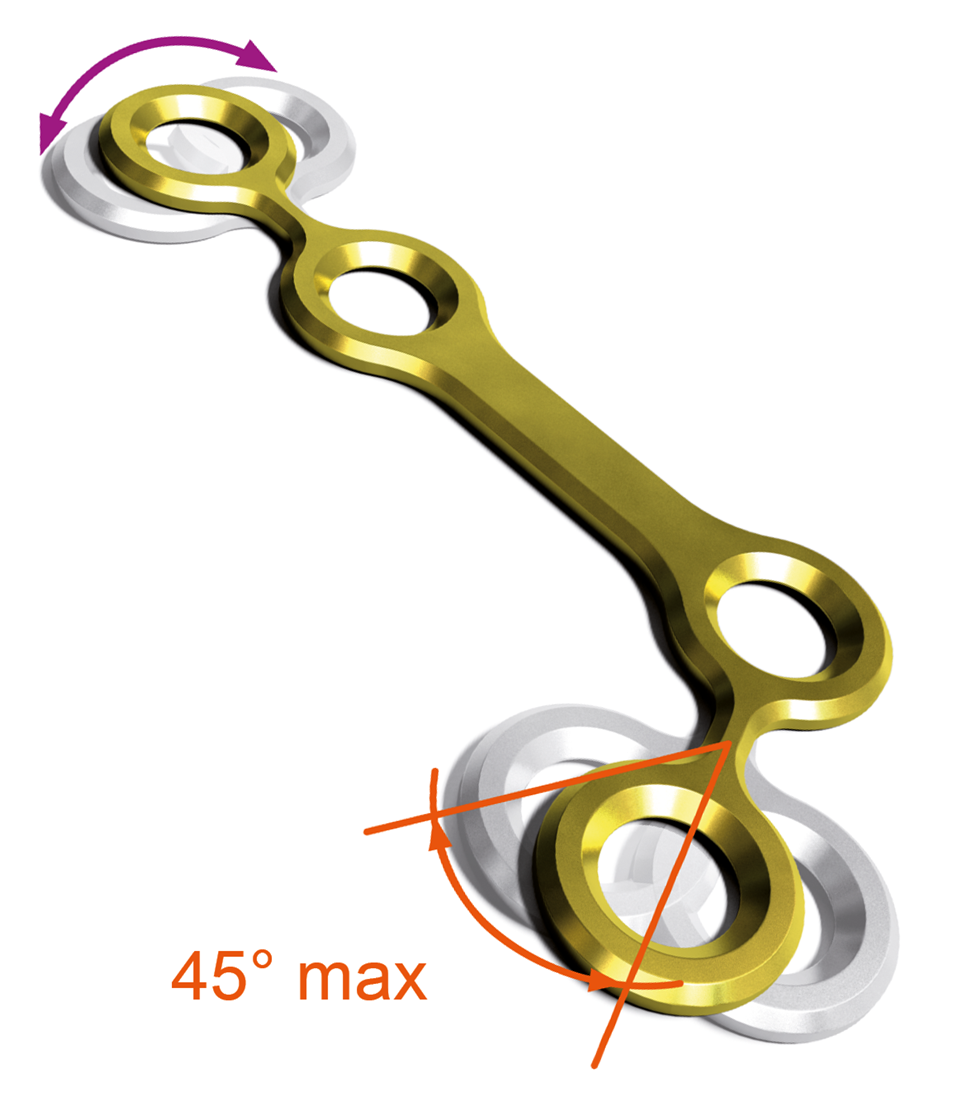

Il s’agit d’un très large panel de vis et de plaques de différentes formes se déclinant dans des épaisseurs et des grades de titane distincts, le tout aisément identifiable grâce à un code couleur.